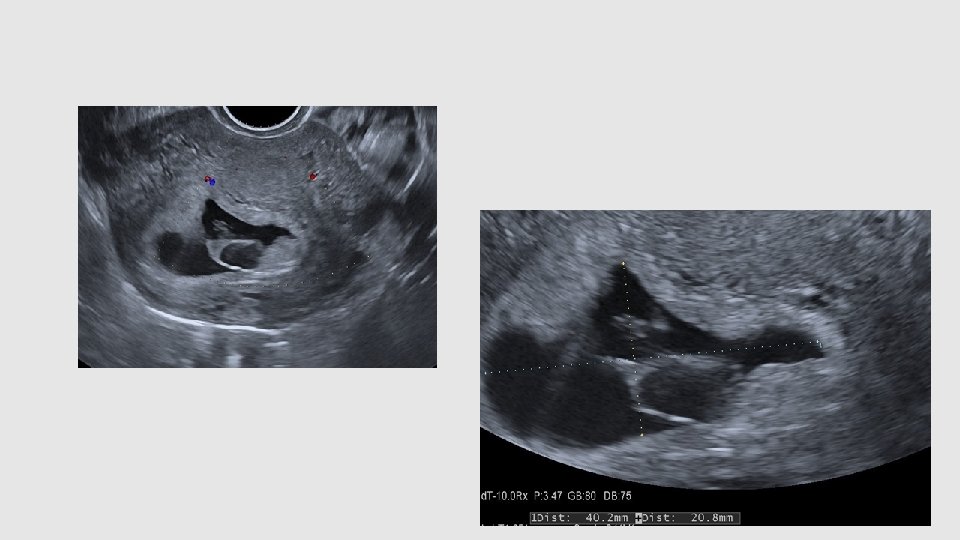

Me B-R. Contrôle clinique RAS Cs 5 semaines après pour douleurs et nausées HCG 615 ui il y a 3 j Corps jaune hemgq Endomètre épaissi Image anéchogène

Me B-R. HCG de contrôle (113 ui) Puis cytotec Contrôle echo à 3 s (oubli) Caillot? Polype? Autre?